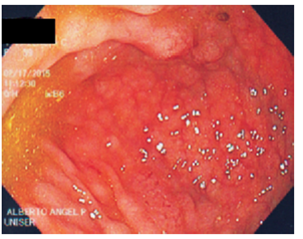

La colonoscopia reporta un pólipo grande en el ciego, de aproximadamente 5 cm de diámetro, que engloba el orificio apendicular, pétreo, del que se toman biopsias. Además, muestra otros múltiples pólipos sésiles de 3 a 15 mm de diámetro, hipervascularizados, con elasticidad conservada, que dan aspecto granuloso a la mucosa a lo largo de todo el colon, incluido el recto. Se toman biopsias. Se hace impresión diagnostica del pólipo gigante en el ciego, para descartar cáncer y poliposis múltiple del colon (Figuras 1, 2, 3 y 4).